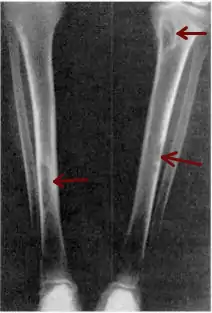

Osteitis fibrosa cystica of the tibia. Arrows point to the brown tumors which are typically present in bones of people with OFC. | |

- Lateral X-ray of the right radioulna showing osteitis fibrosa cystica lesion of ulna diaphysis with a pathologic fracture

X-rays may also be used to diagnose the disease. Usually, these X-rays will show extremely thin bones, which are often bowed or fractured. However, such symptoms are also associated with other bone diseases, such as osteopenia or osteoporosis.[29] Generally, the first bones to show symptoms via X-ray are the fingers.[22] Furthermore, brown tumors, especially when manifested on facial bones, can be misdiagnosed as cancerous.[29] Radiographs distinctly show bone resorption and X-rays of the skull may depict an image often described as "ground glass" or "salt and pepper".[30][31] Dental X-rays may also be abnormal.[2]

The brown tumors commonly associated with OFC display many of the same characteristics of osteoclasts.[23] These cells are characteristically benign, feature a dense, granular cytoplasm, and a nucleus that tends to be ovular in shape, enclosing comparatively fine chromatin. Nucleoli also tend to be smaller than average.[18]